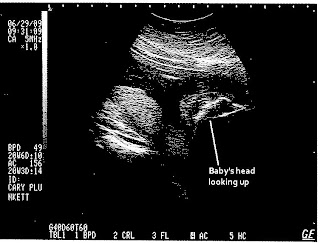

These are at 20 weeks and 6 days. The originals are much clearer but hopefully you get the idea. I'll post some more pictures after our Gender Party on Friday night.